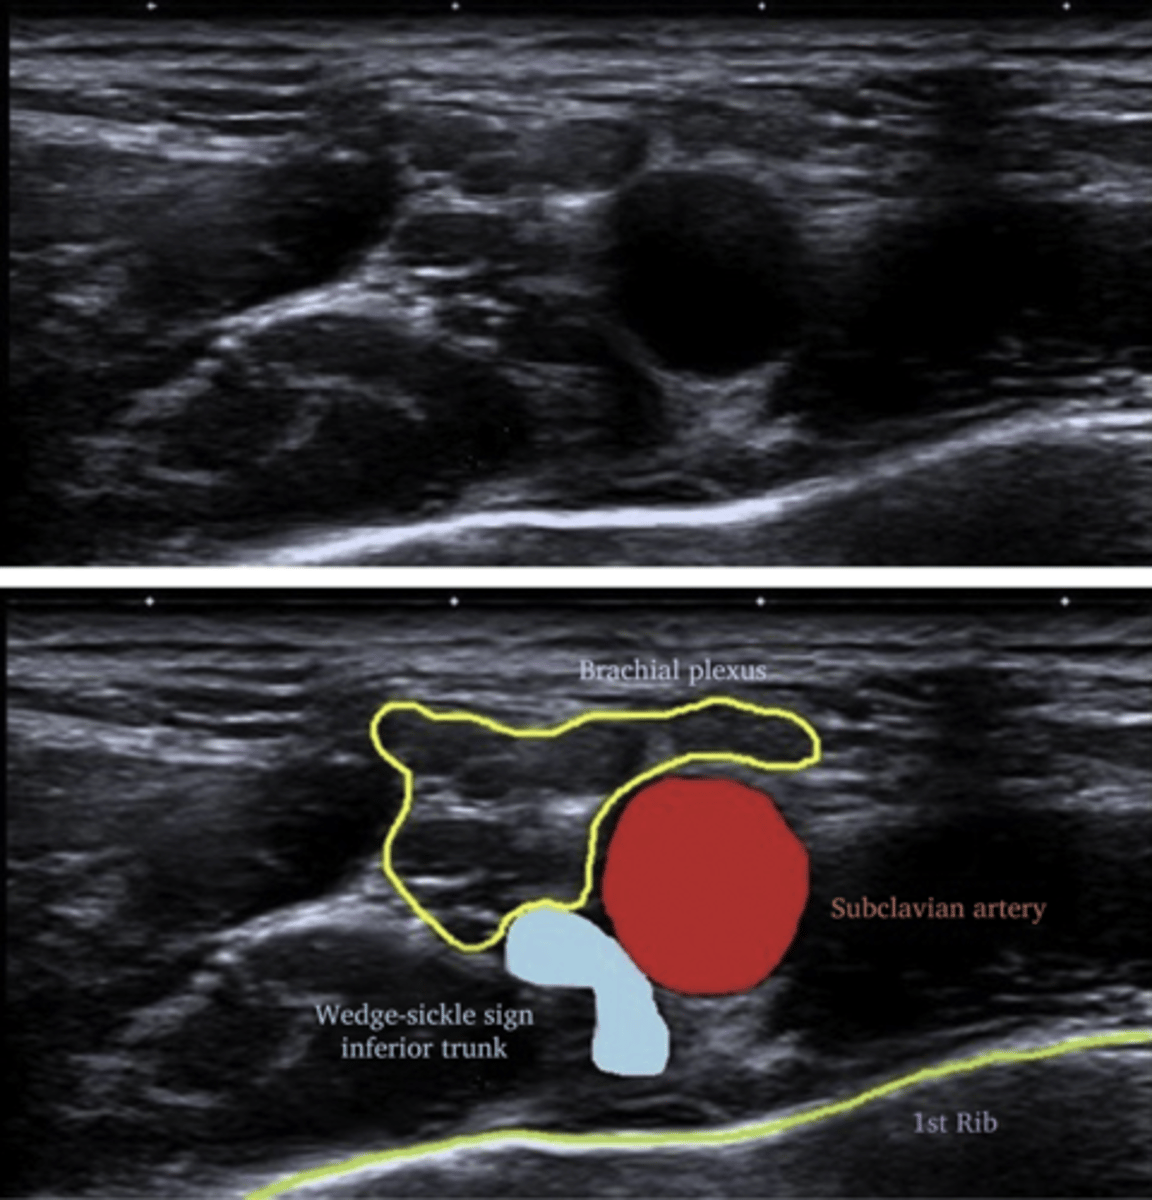

Doppler ultrasound to evaluate subclavian vein for obstruction or thrombosis

Which nerves are evaluated with nerve conduction studies in TOS?

Medial antebrachial cutaneous nerve

and Median motor nerve to the abductor pollicis brevis